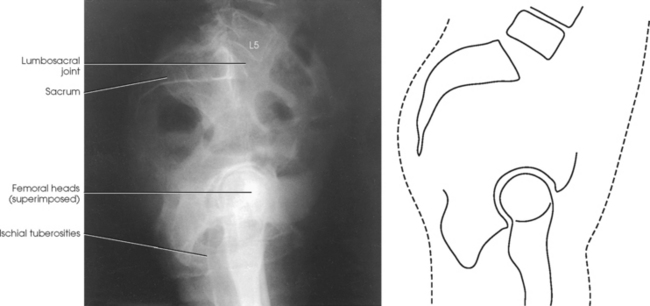

Structures shown: The resulting image shows a lateral radiograph of the lumbosacral junction, sacrum, coccyx, and superimposed hip bones and upper femora (Fig. 7-21).